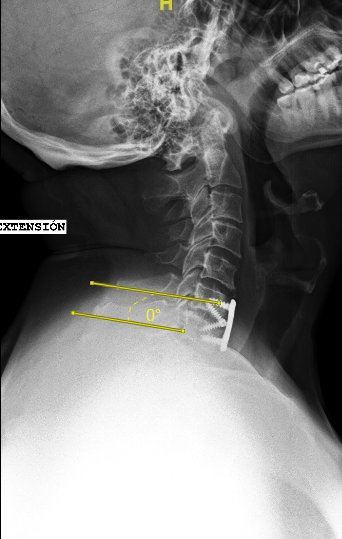

Las RX dinámicas reflejan la ausencia de fusión C6-C7

Las RX dinámicas (6m postop) demuestran estabilidad de la artrodesis